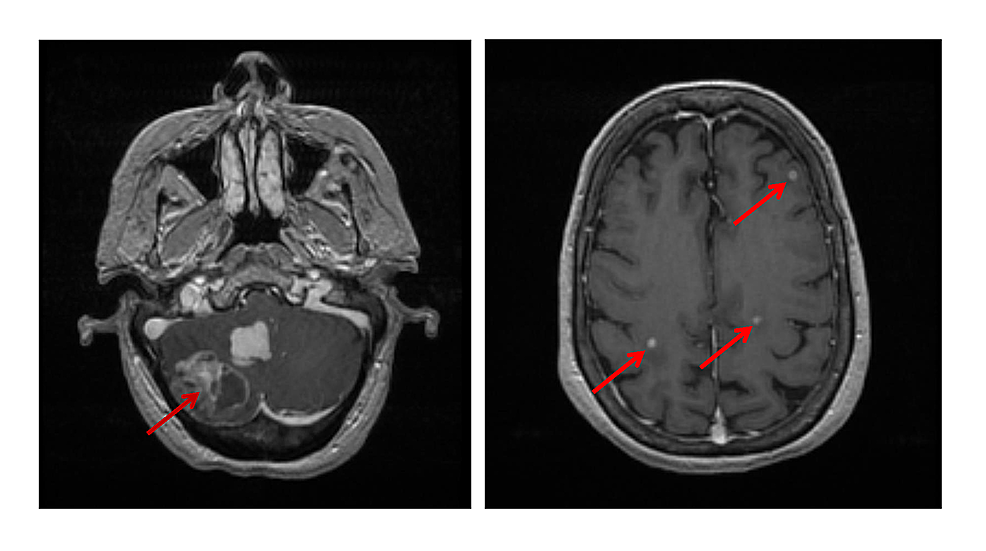

In a recent study, brains we provide services at times that work for you, staying open late and on weekends. A brain lesion appears as a dark or light spot that does not look like normal brain tissues. We are pleased to be able to offer this service to make mri accessible.